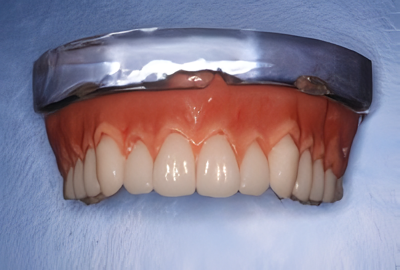

硬いものも噛める、嚙み心地を向上させるコンフォート義歯

入れ歯の痛みでお悩みなら是非ご相談を

とみい歯科医院では、義歯による痛みに悩む患者様に対し、コンフォート義歯の選択肢を提案しています。コンフォート義歯とは、義歯の内面に柔軟性のあるシリコン素材を貼付することで、硬い義歯と歯ぐきの間でクッションの役割を果たし、装着時の痛みを軽減する義歯です。

この構造により、従来の義歯では噛みにくかった硬い食品も快適に噛めるようになるため、食生活の幅が広がります。総義歯・部分義歯のいずれにも対応しており、同医院では試用型の「リーバ」も用意されており、実際の装着感を確かめながら治療を進められます。

自費診療となるため費用は発生しますが、その分の快適性や適合性に対して、多くの患者様から高評価を得ています。義歯の製作には、噛み合わせや口腔内の状態を詳細に確認したうえで、検査や微調整を繰り返し、個々に合ったフィット感を追求しています。

さらに、日常の取り扱いやメンテナンス方法についても丁寧に指導しており、長く快適に使用していただけるよう支援しています。義歯の悩みを抱える方には、一度ご相談されることをおすすめしています。

噛める・外れない新世代入れ歯BPS義歯

金属不使用で審美性抜群

とみい歯科医院では、超精密義歯システムとして知られるBPS義歯を提供しています。BPS義歯は「外れない」「咬める」「痛くない」といった特徴を持つヨーロッパ発の高性能義歯で、従来の義歯に不満を感じていた方に好適です。

複数回にわたる精密な型取りにより、顎の形状や筋肉の動きを反映させ、専門の認定技工士が咬み合わせや形態を繊細に調整して作製します。そのため適合性に優れ、しっかりと咬める上に、装着時の違和感も最小限に抑えられます。

さらに、自然な白さを再現した美しい人工歯を使用しており、見た目にも配慮されています。金属を使用しない設計のため、金属アレルギーの心配もありません。

この義歯は自費診療となりますが、長期間にわたって安定した使用が期待できることから、多くの患者様が満足されています。義歯でお悩みの方には、一度ご相談いただく価値のある選択肢といえるでしょう。

また、BPS義歯は患者様の表情や発音などにも配慮して作られるため、自然な口元を演出できる点も魅力のひとつです。美しさと機能性の両立を求める方におすすめです。